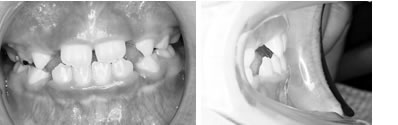

併用した長期経過症例 4歳

治療開始時年齢は6歳半でしたが、永久歯は1本もありませんでした。右上の乳歯Dから左上の乳歯Cまでが反対咬合の状況でした。

レントゲンの検査、家族暦などから骨格的な下顎前突の程度が大きいことがわかりましたので、オトガイ帽装置(チンキャップ)を使用することになりました。

この装置の使用効果についてはさまざまな論拠、発表がありますが、本院では直接的に下顎骨を小さくする効果は無いと考えています。しかしながら、他の装置の使用効果を高めたり、習癖を除去する効果があり、その結果上顎の本来の成長が得られて上下顎の大きさのバランス改善が得られると思われます。少しでも治療を楽しむため色付の装置も用意しています。

普段のかみ合わせのまま下顎を後ろに押し下げようと力をかけた場合、上顎前歯と下顎前歯がぶつかって上顎まで後ろに下げようとする力が働いてしまいます。そこで、チンキャップを使用する場合には前歯の干渉を避けるためにクリアプレートを併用しました。

1年後(7歳半)の口腔内 下顎前歯が抜け替わりましたが、反対咬合の状態です。

装置使用開始4ヶ月目には反対咬合が解消されています。